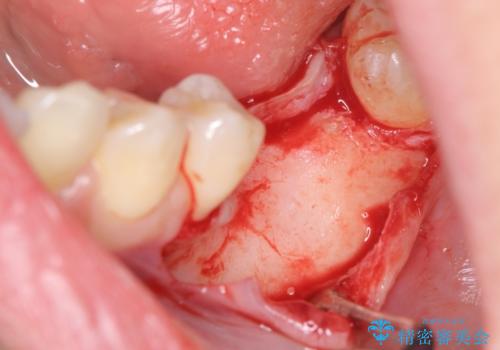

- 他院で抜歯後放置してしまった左下の奥歯の機能・見た目の回復を希望され来院されました。

放置したことによる影響か骨が吸収し、インプラント周囲に十分な骨が確保できないような状況であったため骨造成を併用したインプラント治療を計画します。

インプラントを用いて機能回復を行うことで、奥歯がしっかりと噛めるようになります。

周囲に骨があることでより長期的な予後を見込むことができます。